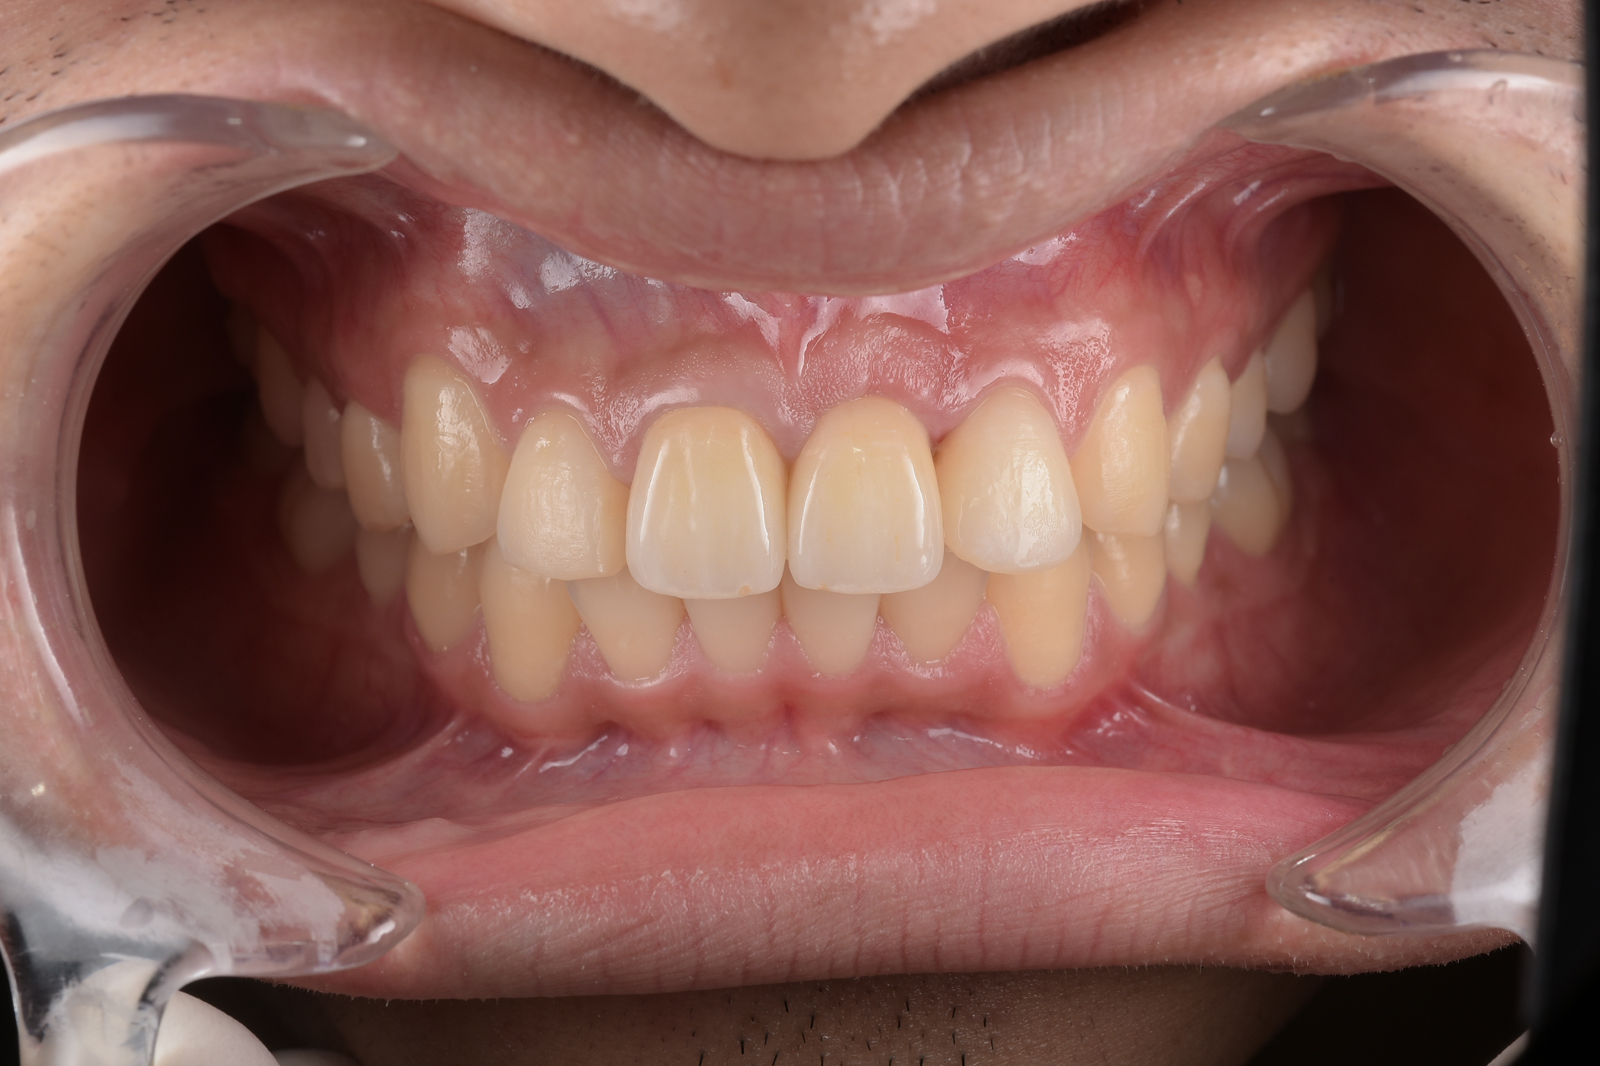

重度の虫歯で失われた、上あご全体の歯を包括治療した症例。